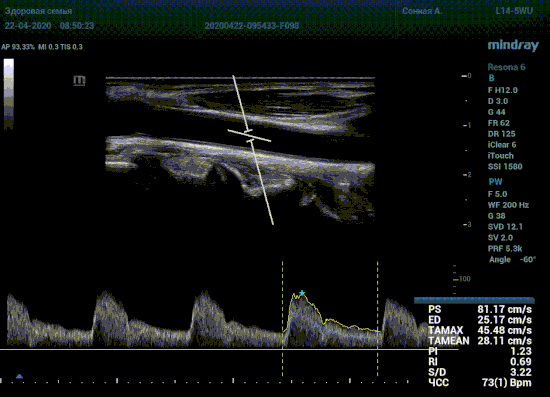

Ангиосканирование, на сегодняшний день, неотъемлемая часть медицинской практики. Широко используется в сосудистой хирургии, терапии и, в частности, кардиологии. Наибольшее значение в ультразвуковой ангиологии имеет оценка допплеровского спектра. Режим Pulse Wave Doppler (PWD) есть в каждом современном приборе.

Измерения скоростей в артерии, анализ формы спектра, его планиметрия с расчетом показателей это рутинная процедура. Её повторяют в течении рабочего дня множество раз. Компания Mindray оценила траты времени на данные процедуры и внесла вклад в работу специалиста.

Алгоритм проводит измерения в режиме реального времени, выдавая результаты прямо на ходу. Не отвлекаясь на переключение режимов, остановку сканирования для измерений, а также ручной планиметрии спектра, достаточно просто нажать кнопку в калькуляторе с названием нужной артерии. Все значения сразу же попадут в отчет прибора, готовый к печати.

Особо ценна данная функция при исследовании тяжести стеноза. Доктор проводит санирование методом «утюжка» или же проводит «прогулку по стенозу» смещая зону опроса импульсно-волнового допплера. Таким образом проводит поиск максимальную скорость в струе элайзинга. Ранее максимальная скорость определялась на глазок, с дальнейшим измерением, либо серией измерений вручную. Теперь прибор сделает всё сам, без отрыва от движения, автоматически измеряя её в режиме реального времени.

Какие показатели выдает автоматический расчет? Доктор может настроить расчет под себя, под свои собственные желания. Стандартно выставлены показатели пиковой (PS) и конечной диастолической скорости (ED), TAMAX, TAMEAN, Pi, Ri, S/D соотношение и ЧСС. Можно дополнить из списка показателей: MD, PPG, Объемный поток, DT, AT, MPG, MMPG, VTI, D/S соотношение. Прибор подстраивается под Вас, а не вы под прибор.